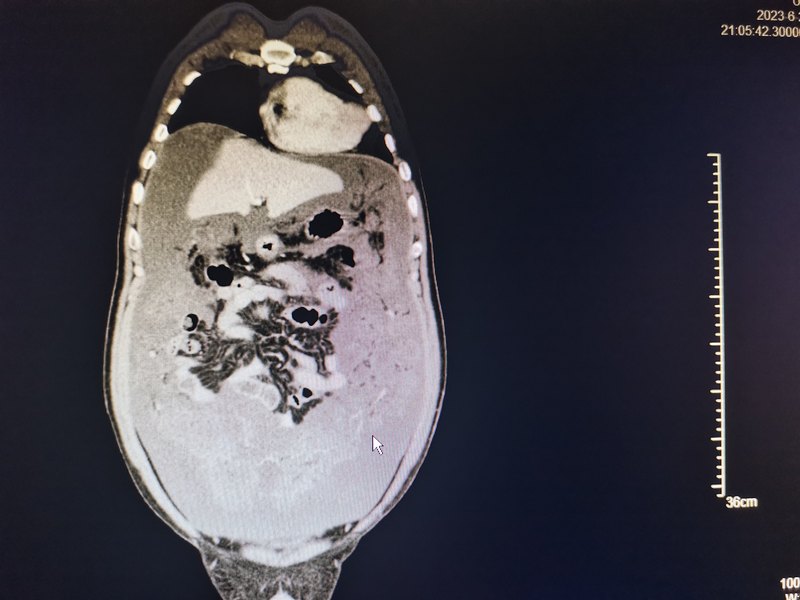

不可小觑的阑尾肿瘤

阑尾炎一般认为是小病,但是阑尾肿瘤可不能小觑。这一个月遇到了三例阑尾肿瘤,其中1例为早期,肿瘤局限于阑尾内,另外2例出现腹膜腔广泛种植转移,形成腹膜假粘液瘤。早期阑尾肿瘤一般都主张根治性的手术治疗,治疗效果比较满意。一旦出现腹膜腔的种植转移就属于晚期了,但也不要轻易放弃。对于晚期肿瘤可以在手术减瘤的基础上进行腹腔热灌注化疗和全身的化疗免疫治疗以及靶向治疗以延长病人的生命,改善生活质量。